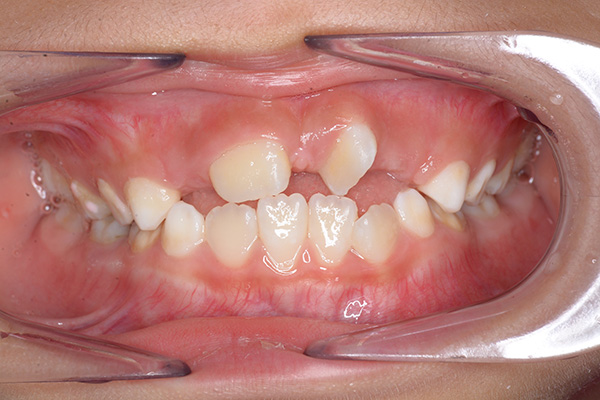

| 主訴 | 上顎前歯のでこぼこ | 診断名 | アングルⅡ級叢生症例 | ||||

| 既往歴として上顎正中過剰歯(2本)は抜去済み。その影響で上顎右側中切歯は捻転して萌出しており、下顎右側中切歯と早期接触が認められたため2x4(上顎のみブラケット装着)にて前歯部の改善を行った。現在は永久歯列完成まで経過観察を行い、希望があれば口元の突出感を改善するために本格矯正治療を行うことにしている。 | |

| 批評・予后 | 早期治療によって前歯部の咬合干渉は回避され、その後の永久歯への交換は順調である。 |